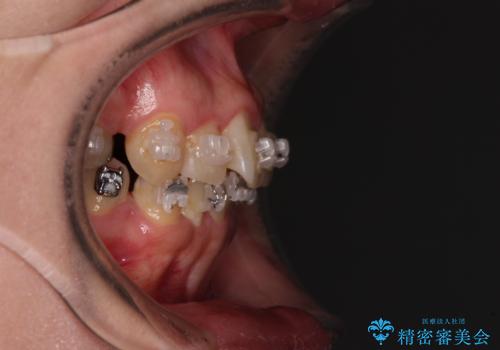

- 海外で抜歯矯正を開始し、治療途中で帰国したため、転院先を探しているとのことで来院された患者様です。

ワイヤーは抜けてしまい、後戻りが始まっている状態でしたが、既存の装置を継続利用して受け入れてくれる医院が見つからないとのことでした。

当院では、張り替える必要のある部位は張り替えることで継続することとし、抜歯スペースを閉じていくように治療を行うこととしました。